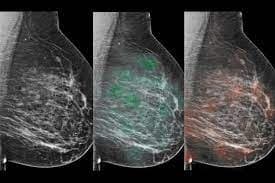

AI-supported mammogram screening : चैटजीपीटी के आने के बाद हर क्षेत्र में अब आर्टफिशियल इंटेलीजेंस यानी एआई के इस्तेमाल की चर्चा शुरू हो गई है. यह नतीजे भी अच्छे दे रहा है. हाल ही में एक अध्ययन से पता चला है कि मानक स्क्रीनिंग की तुलना में कृत्रिम बुद्धिमत्ता (एआई) द्वारा समर्थित मैमोग्राफी स्क्रीनिंग से स्तन कैंसर के ज्यादा मरीजों की पहचान हुई. इससे विकिरण चिकित्सकों (रेडियोलॉजिस्ट) के स्क्रीनिंग रीडिंग का कार्यभार लगभग आधा हो गया. ‘द लांसेट ऑन्कोलॉजी’ जर्नल में प्रकाशित एक नये शोध में यह जानकारी सामने आयी है. स्वीडन के लुंड विश्वविद्यालय के नेतृत्व में किये गए अध्ययन से पता चला कि स्तन कैंसर की जांच के लिए एआई-समर्थित मैमोग्राफी, मानक डबल स्क्रीनिंग के विकल्प के रूप में ज्यादा सटीक, सुरक्षित और कुशल है.

शोध में अध्ययन के लिए लगभग 80,000 महिलाओं को शामिल किया गया तथा उन्हें दो अलग-अलग समूहों में बांट दिया गया. 40,003 महिलाओं के एक समूह को एआई-समर्थित स्क्रीनिंग तथा 40,030 महिलाओं के दूसरे समूह को मानक स्क्रीनिंग प्रक्रिया से गुजारा गया. शोध में एआई-समर्थित स्क्रीनिंग से 244 महिलाओं (28 फीसदी) में कैंसर पाया गया, जबकि मानक स्क्रीनिंग से 203 महिलाओं (25 फीसदी) में कैंसर का पता चला. शोध के परिणामस्वरूप एआई समर्थित स्क्रीनिंग से कैंसर के 41 अधिक मरीजों का पता चला.

विश्वविद्यालय में डायग्नोस्टिक रेडियोलॉजी में प्रमुख शोधकर्ता और सहायक प्रोफेसर क्रिस्टीना लैंग ने कहा, हमने पाया कि एआई का उपयोग करने से मानक स्क्रीनिंग की तुलना में फाॅल्स पॉजिटिव को प्रभावित किये बिना 20 फीसदी (41) अधिक कैंसर मरीजों का पता चला. स्क्रीनिंग में फाॅल्स पॉजिटिव तब होता है जब एक महिला को फिर से बुलाया जाता है लेकिन स्क्रीनिंग के बाद उसे कैंसर के संदेह से मुक्त कर दिया जाता है.

शोधकर्ताओं ने कहा कि दोनों अध्ययन में फाॅल्स पॉजिटिव दर डेढ़ फीसदी थी. इसके अलावा, रेडियोलॉजिस्ट के लिए स्क्रीन-रीडिंग कार्यभार में 44 फीसदी की कमी पायी गई. अध्ययन में एआई-समर्थित स्क्रीनिंग, मानक स्क्रीनिंग 83,231 की तुलना में 46,345 थी.